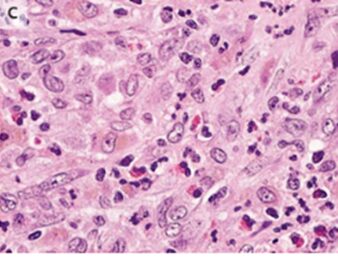

胸部X-pでは左肺に気胸と両肺の透過性低下を認めた(A)。

胸腔ドレーン挿入後の胸部CTでは主に上肺野と中肺野に複数の嚢胞と結節が示唆され、肋横隔角は温存されていた(B)